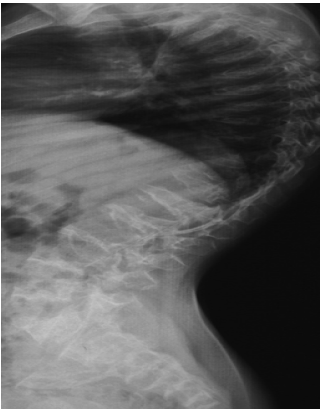

In accordance with the aforementioned clinical features, the radiological phenotype has been performed to further interpret the constellation of the skeletal abnormalities. Lateral thoracic spine radiograph of a-six-year-old-boy with SMD (Kozlowski type) showed generalized platyspondyly (flat vertebral bodies) (a). AP hand radiograph of a-12-year-old-boy with SMD (Kozlowski type) showed small carpal bones, retardation of the carpal ossification’s centres with minimal metaphyseal changes of the short tubular bones which look short and broad. Note marked metaphyseal dysplasia of the inferior ends of the radius and ulna (Figure 2a and b). Lateral spine radiograph of a -13-year-old-girl with the diagnosis of SMD type Kozlowski showed evident generalized platyspondyly with anterior wedging (a). Note, severe kyphoscoliosis deformity. (kyphosis - 70◦ Cobb and scoliosis - 55◦ Cobb) (Preoperative radiographs) (Figure 3a and b). Postoperative spine radiographs showed correction kyphoscoliotic deformity - «growing rod» construction. For 5 years the patient performed staged operations. final correction kyphoscoliotic deformity - final posterior fusion Th2-L5. Posterior spondilodesis (Figure 4a and b).

Figure 3: a) Lateral spine radiograph of a -13-year-old-girl with the diagnosis of SMD type Kozlowski showed evident generalized platyspondyly with anterior wedging. b) Note, severe kyphoscoliosis deformity. (kyphosis - 70◦ Cobb and scoliosis - 55◦ Cobb)( Preoperative radiographs).